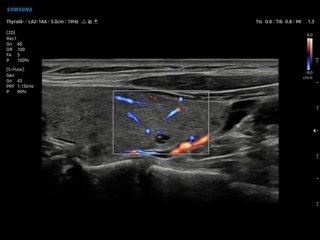

- LA2-14A — линейный датчик;

- S-Detect Thyroid — программа автоматического обнаружения образований и анализа щитовидной железы, измерение и классификация по системе системе TI-RADS;